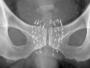

転移のない前立腺がんの根治を目指し、小さな放射線源を前立腺内に埋め込む「密封小線源療法」が国内に導入されてから20年以上たった。長年にわたる患者の追跡で、前立腺の全摘手術や体外からの放射線治療(外照射)と同等の優れた長期成績が示されている。手術に比べ体の負担が少ないなど利点の多い治療法だが、近年は症例数が減少傾向にある。治療の選択肢が増える中、患者に利点が伝わっていない可能性があるという。